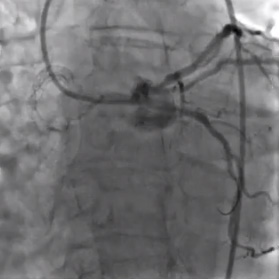

Angiograma inicial

Diagnóstico

• El electrocardiograma mostró bradicardia sinusal con un infarto inferior previo.

• La angiografía coronaria izquierda muestra óstiums separados de la arteria descendente anterior y circunfleja.

• La arteria circunfleja tenía un flujo de TIMI-2. Hubo una estenosis subtotal de alto grado en su parte proximal.

• Con alguna dificultad, se utilizó un catéter guía adicional de 6F para intubar la arteria circunfleja.